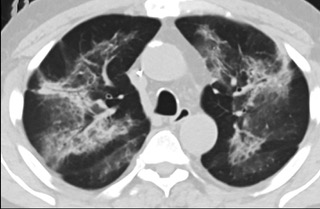

疑點(diǎn)一,電子煙患者的CT影像和臨床表現(xiàn)并不具有特異性。所謂美國電子肺炎患者,其實(shí)是對沒有其他合理診斷證據(jù)、吸食電子煙肺炎患者的統(tǒng)稱。這些患者在病發(fā)前90天內(nèi)吸食了電子煙,尤其值得注意的是,部分患者的CT影像特征和臨床表現(xiàn)與病毒性肺炎患者極其相似。

中、下肺軸位CT平掃顯示毛玻璃樣混濁伴胸膜下保留。(同一病人CT影像)